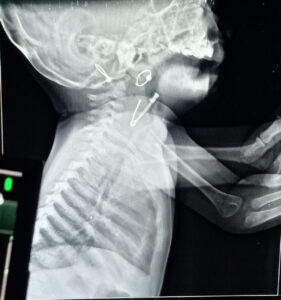

दापोली तालुक्यातील वणंद गावातील एका सात महिन्याच्या बाळाला एका महिन्यापासून सर्दी खोकल्याचा त्रास होत होता. त्यासाठी बाळाच्या आई- वडिलांनी दापोली येथील बालरोगतज्ज्ञांना दाखविले असता त्यांनी एक्स-रे काढण्याचा सल्ला दिला. एक्स-रे मध्ये घशामध्ये सेफ्टी पिन अडकल्याचे निदर्शनास आले व बालरोग तज्ज्ञांनी त्वरित पेशंटला डेरवण येथील वालावलकर रुग्णालयात जाण्यास सांगितले. वालावलकर रुग्णालयात येताच कान -नाक -घसा विभागाच्या डॉ. सीजा यांनी पेशंटला तपासले व प्राथमिक तपासणी करून घेतली. क्षणाचाही विलंब न करता पेशंटला ऑपरेशन थेटरमध्ये घेण्यात आले व कान-नाक-घसा विभागाचे तज्ज्ञ डॉ. राजीव यांनी युसोफॅगोसकोपी करून सेफ्टी पिन काढण्यात यश आले. सेफ्टी पिन उघडी असल्याकारणाने ती अन्ननलिकेसाठी धोकादायक होती म्हणूनच ती लवकरात लवकर बाहेर काढण्याची गरज होती. तसेच एक्स-रे मध्ये ती घशामध्ये दिसत होती. परंतु ऑपरेशनला घेईपर्यंत ती अन्ननलिकेत गेली होती. त्यामुळे हे अति जोखमीचे ऑपरेशन डॉ. राजीव व डॉ.सीजा यांनी लीलया पार पाडले. तसेच सात महिन्याच्या बाळाला भूल देण्याचे अतिशय अवघड काम रुग्णालयाच्या भूल तज्ज्ञांनी कुशलतेने केले व ऑपरेशन नंतर लागणारे लहान मुलांचे आयसीयू याठिकाणीच असल्याकारणाने ऑपरेशन नंतरची रिकव्हरी सुखकर झाली. कान-नाक-घसा तज्ज्ञ, भूलतज्ज्ञ, बालरोग तज्ज्ञ अशा तज्ज्ञांच्या एकत्रित प्रयत्नांनी सात महिन्यांच्या चिमुकलीला जीवनदान मिळाले. सद्यस्थितीत या चिमुकलीची प्रकृती उत्तम असून काही दिवसात तीला घरी सोडण्यात येईल.